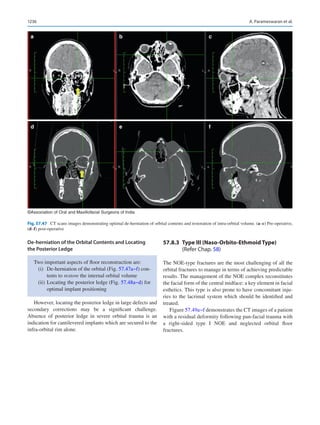

map genomes and mutations, our ability to interpret cancer

biology has had a meteoric rise even in the last decade. This

leads to personalizing management via either chemotherapy

or radiotherapy with predictable success making most can-

cers chronically manageable diseases rather than a death sen-

tence. The future of personalized medicine will most likely

put the cancer surgeon out of an occupation.

He introduced a study that demonstrated how a serendipi-

tous finding in mice with Treacher-Collin’s syndrome treated

for endometrial cancer with a chemotherapeutic agent

knocked out the gene causing the craniofacial anomaly in the

following generation. This suggested that we could poten-

tially be looking at gene therapy for craniofacial anomalies,